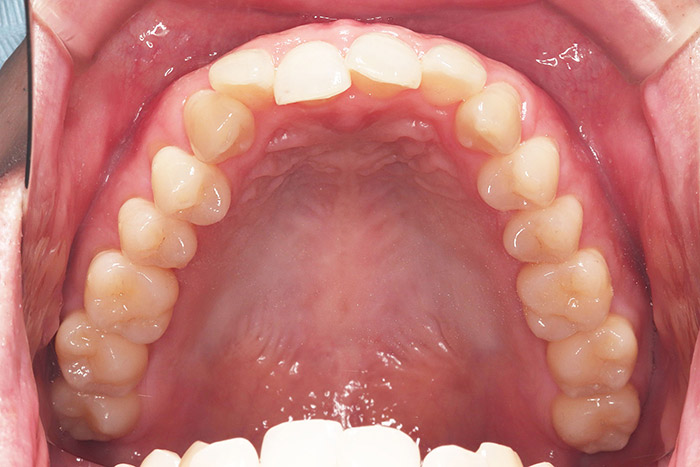

K様

治療前

年齢 27歳

性別 女性

治療名称 マウスピース型カスタムメイド矯正歯科装置(インビザライン)・コンプリヘンシブパッケージ(フルパッケージ)

総額治療費用 770,000円(税込10%) 金額備考 精密検査料・診断料 33,000円(税込10%)

治療期間 1年11か月 通院頻度など 40日ごと

1枚につき10日装着を指示しました。

治療内容

患者の症状 上顎前歯の前突、八重歯

治療方法 上下左右の第一小臼歯抜歯で、マウスピース型カスタムメイド矯正歯科装置による矯正

治療結果 上顎前歯の前突、八重歯が改善されました。

歯並びをより良くするために追加でアライナーを発注しました。

リスク/副作用 決められた時間装着する必要があります。